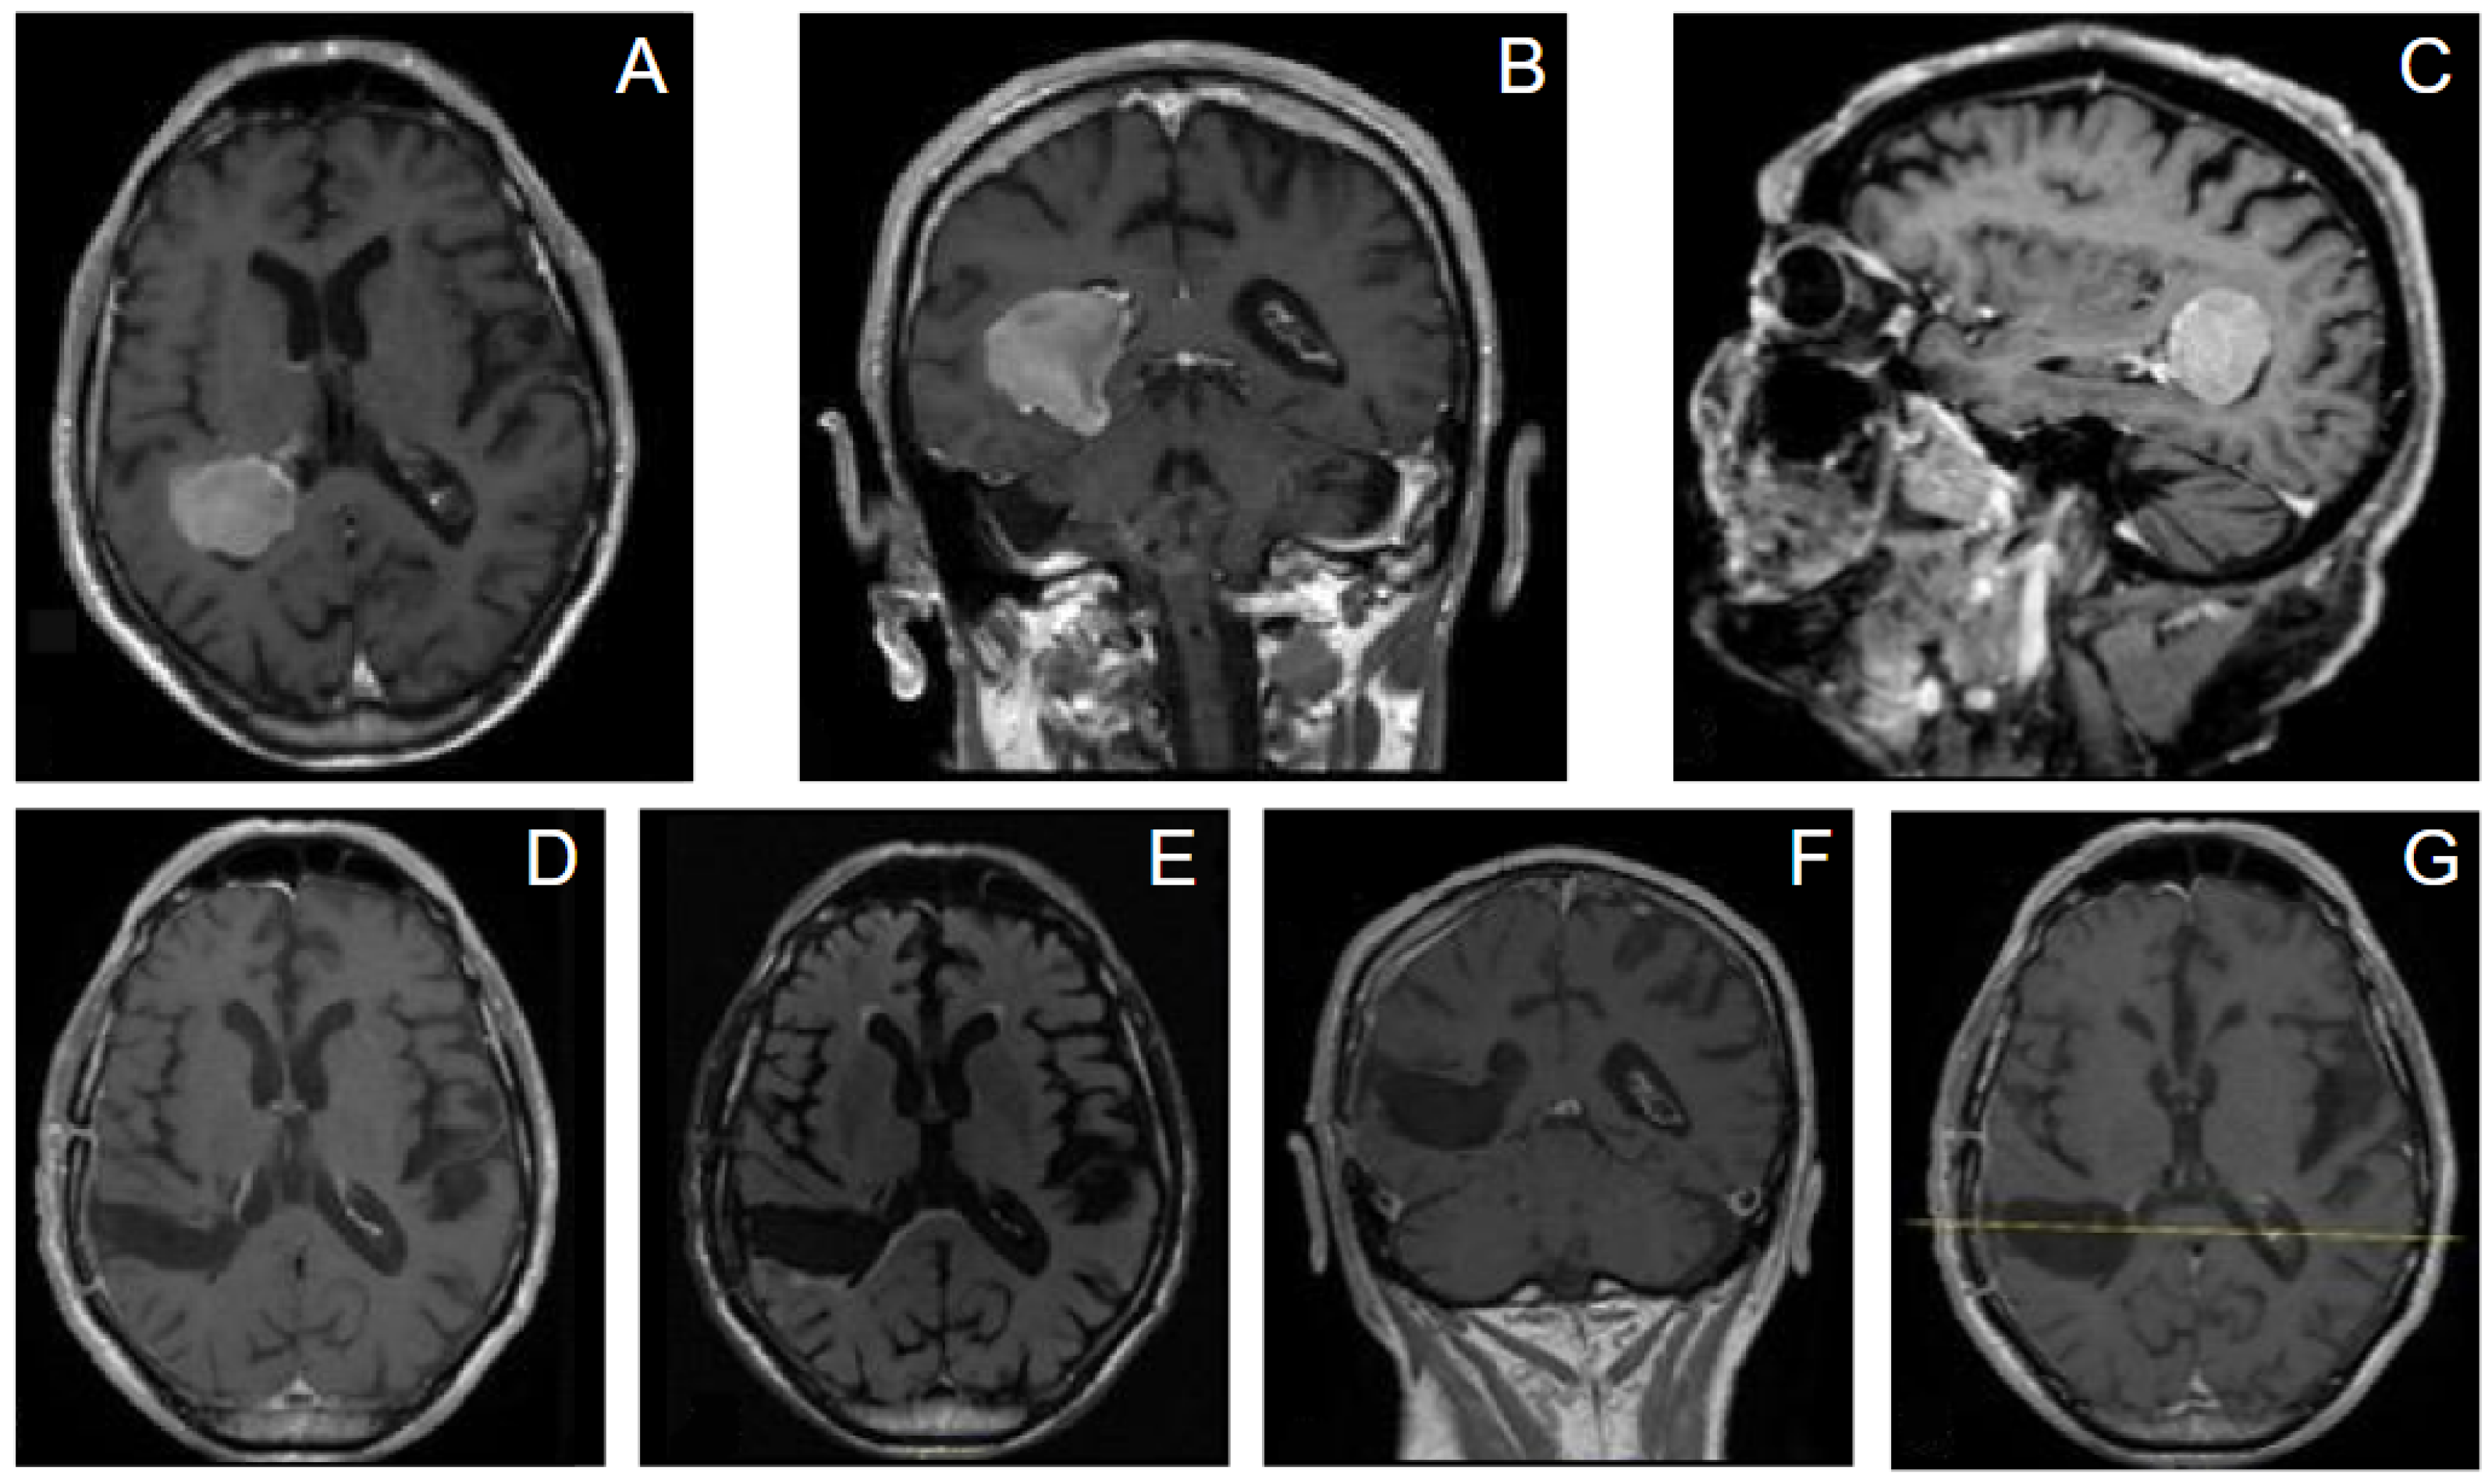

- Case 1. An 83-year-old man presented with a history of loss of consciousness episodes and ideomotor slowdown. He was otherwise neurologically intact. MRI revealed a large right-sided intraventricular mass in the trigone of the right lateral ventricle consistent with meningioma. We adopted for the patient a supine position, and a minimally invasive tumor excision was performed using the tubular retractor system assisted by neuronavigation. Gross total resection (GTR) was achieved and pathology confirmed WHO grade 1 meningioma. He had an uneventful recovery and remained neurologically intact after surgery. At 3 months from surgery there was no evidence of tumor recurrence, and no evidence of brain injury or progressive neurological deficits (Figure 6).